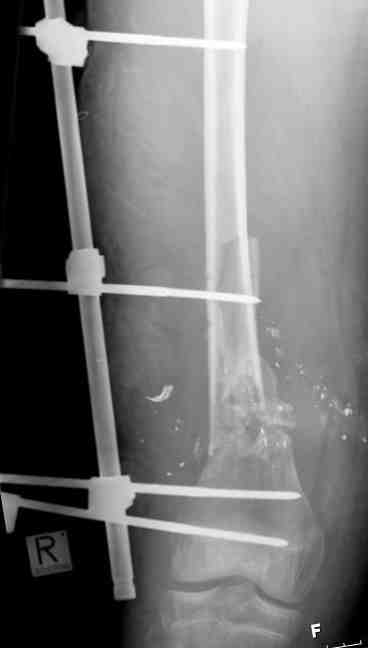

Выше представлены рентгенограммы открытого оскольчатого перелома нижней трети голени

X-rays of Compound Comminuted # Distal/3 Lt Tibia

Операционные снимки перед и после наложения аппарата Илизарова

In operation room before and after Ilizarov apparatus has been applied

Послеоперационные рентгенограммы

Postoperative X-rays

В нижнем ряду представлены рентгенограммы после окончательной репозиции.

And final reduction after Hexapod program has been finished